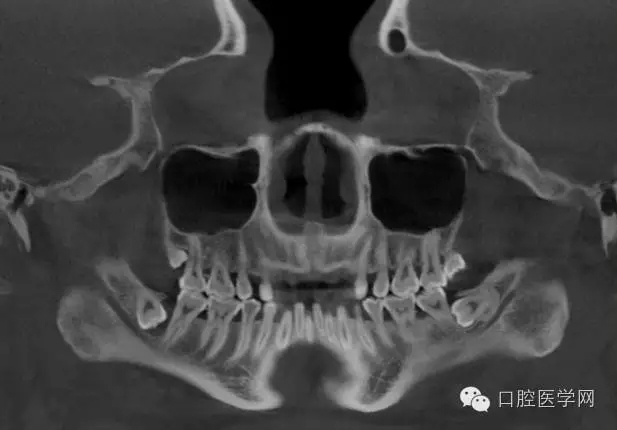

4.阻生牙

最常見于下頜第三磨牙

X線表現(xiàn):確定阻生牙的位置;確定阻生方向;牙根數(shù)目和形態(tài);阻生牙有無齲齒和根尖情況;與第二磨牙的關(guān)系;與下頜管的距離和磨牙后間隙的大小。